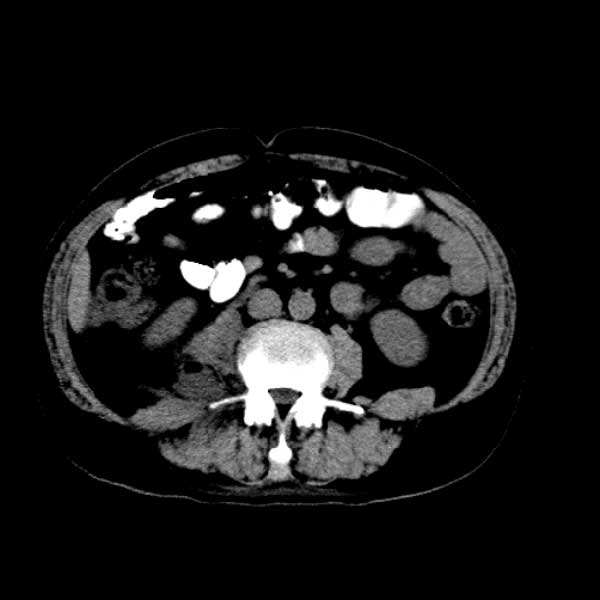

标题: CT13513:男 71 腹部疼痛20余天,近几天高热就诊,骨窗未见异 [打印本页]

标题: CT13513:男 71 腹部疼痛20余天,近几天高热就诊,骨窗未见异

考虑右侧腰大肌脓肿,向右髂窝、右腹股沟流注。

支持化脓性阑尾炎伴右髂窝脓肿、腰大肌腰方肌脓肿形成。

考虑腹腔及盆腔化脓性炎症,累及右侧髋关节及腹股沟区.

首先考虑化脓性阑尾炎伴腰大肌、腰方肌脓肿,不除外回盲部结核。

回盲部癌待排除。

患者肠镜检查考虑结肠癌,病理证实

患者肠镜检查考虑结肠癌,病理证实。肺部ct可见多发结节,考虑转移